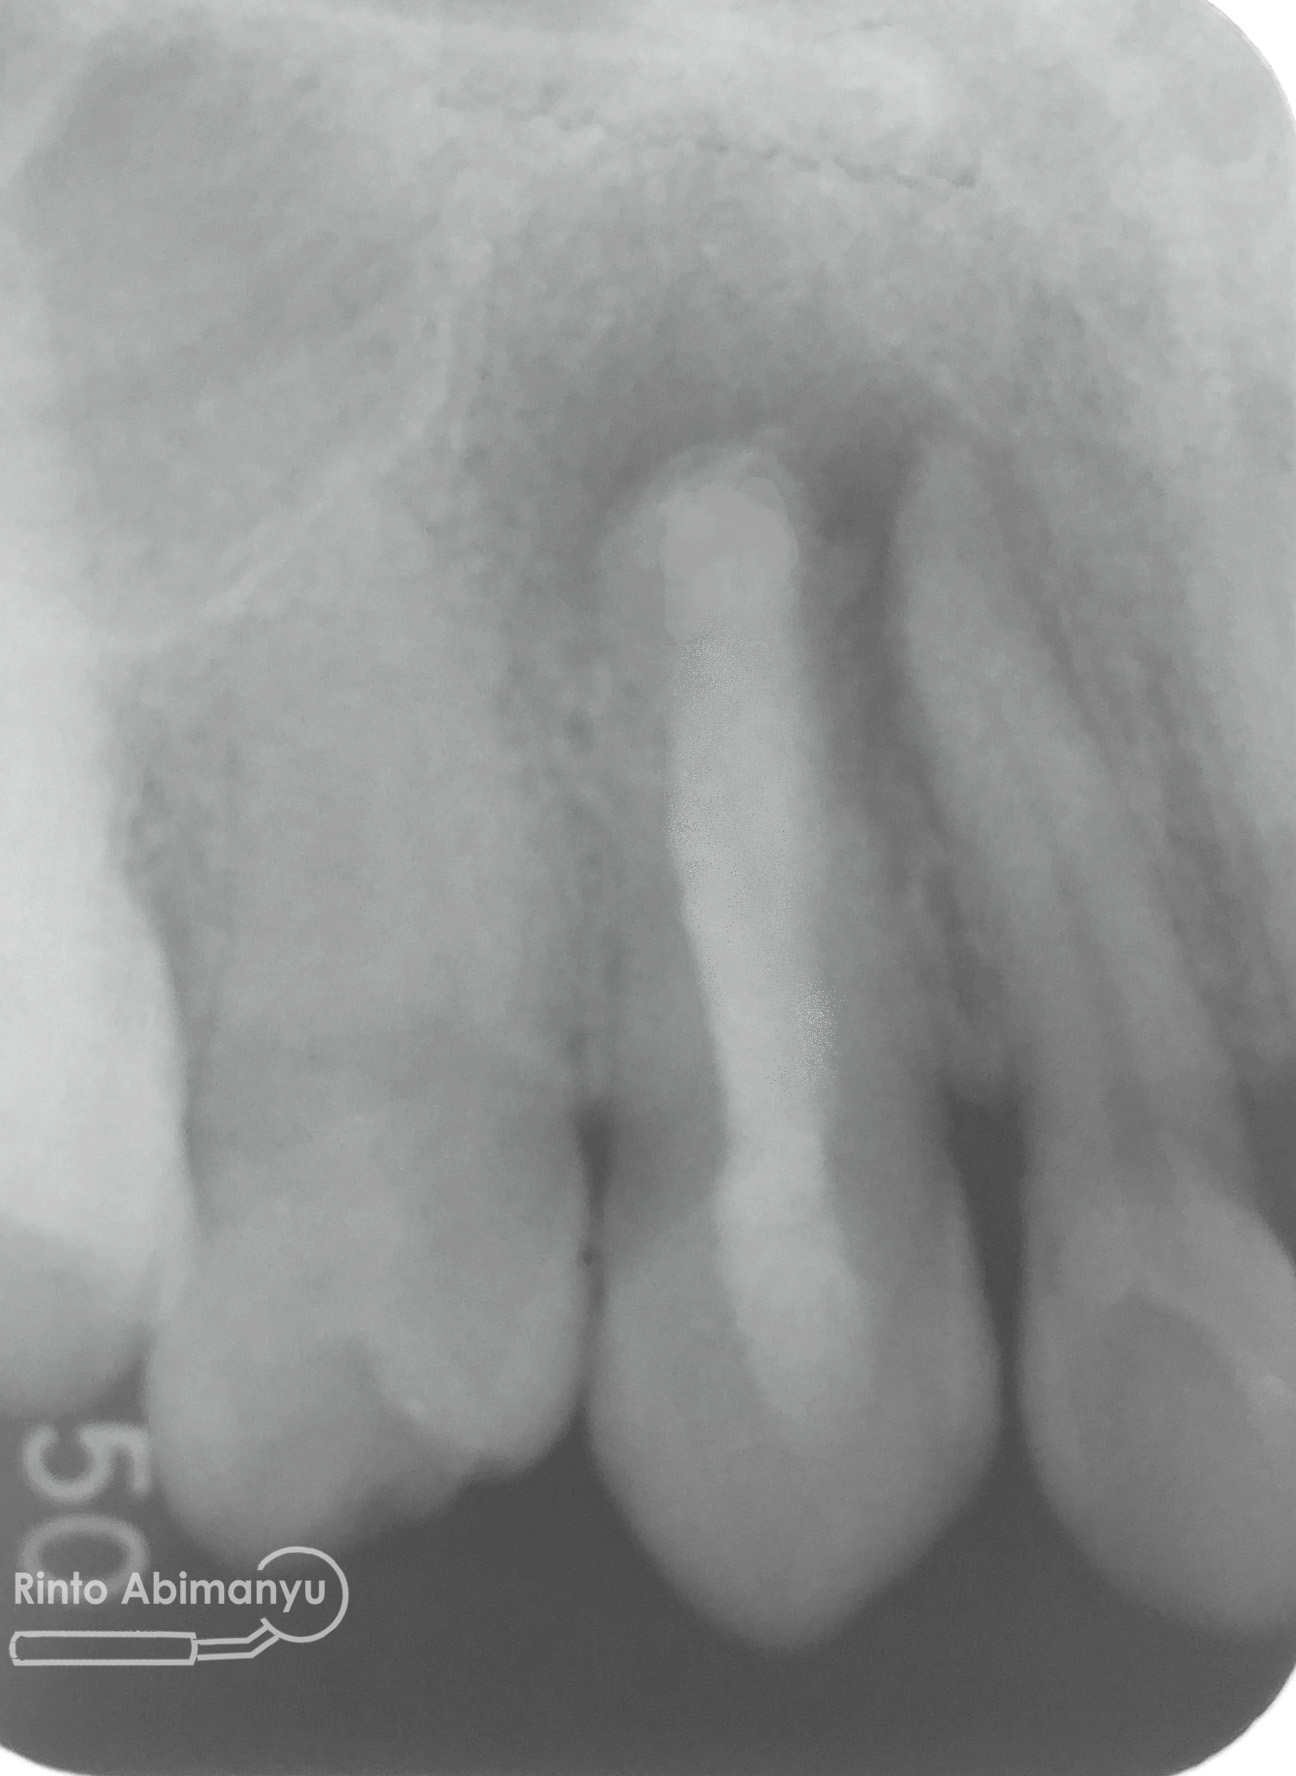

Setelah itu dilakukan pengambilan ronsen kembali…

Alhamdulillah perawatan ini tidak ada kendala dan bisa diselesaikan dalam satu kali kunjungan langsung dua gigi… Ronsen sangat penting dalam prosedur perawatan saluran akar, jadi pesan saya adalah “No Xray, No Endo” 🙂